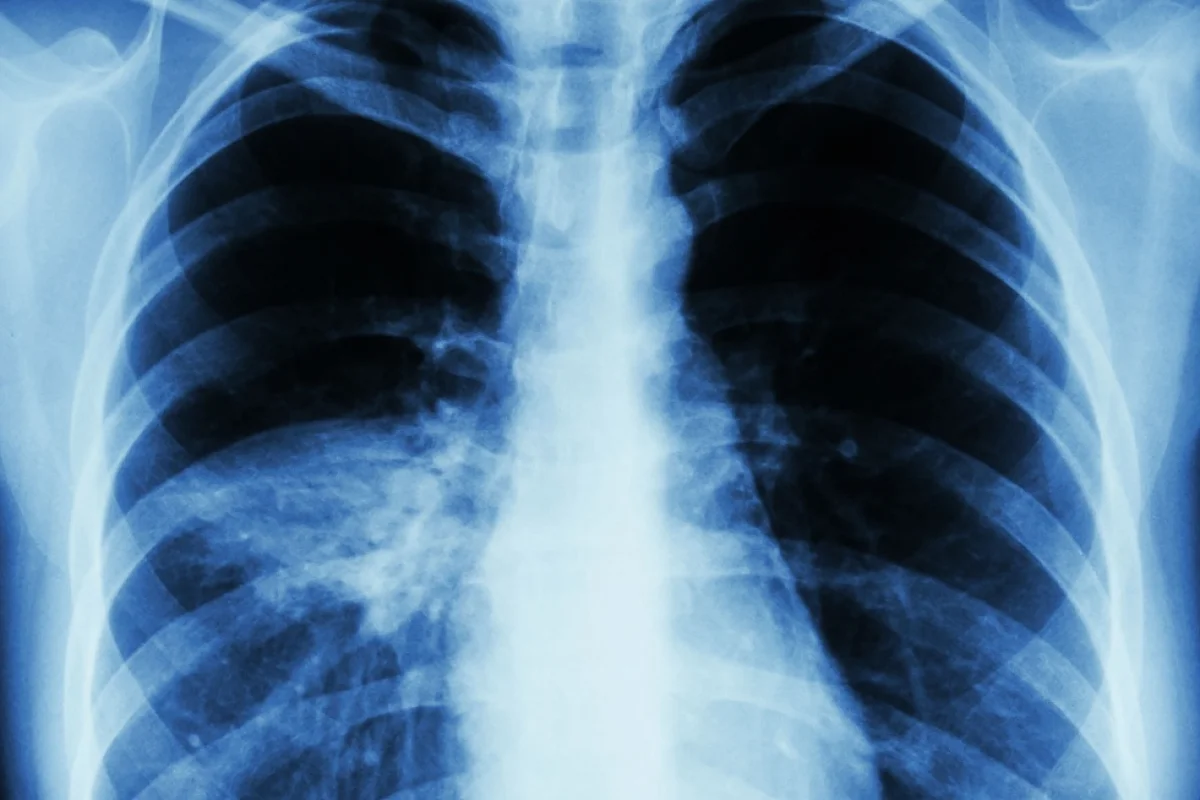

How Pneumonia Is Typically Diagnosed

Doctors use a few ways to figure out if you have pneumonia. They look at your medical history and do a physical check. They also listen to your lungs with a stethoscope.

As

“The diagnosis of pneumonia is often suggested by the clinical presentation, but imaging is critical for confirmation,”

states

Medical Expert, an expert in infectious diseases

. Chest X-rays are often used to see if you have pneumonia and how bad it is.

Importance of Chest X-rays and Advanced Imaging

Chest X-rays are vital for diagnosing pneumonia, even with unusual symptoms. They show signs of pneumonia like infiltrates or consolidations. Sometimes, computed tomography (CT) scans are used for more detailed views of the pneumonia.